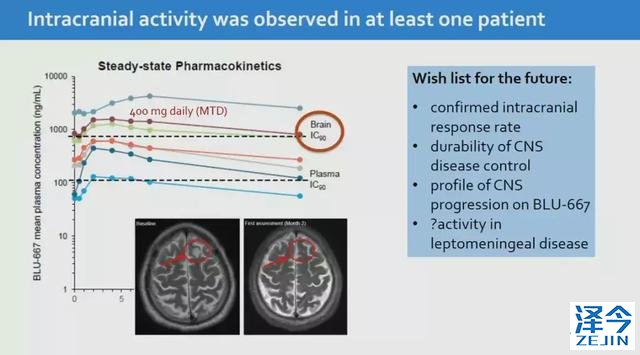

2

一位转移性NSCLC患者在接受治疗后“首次评估时脑部响应”。

除BLU-667外,目前处于I期评估的另一种选择性RET抑制剂是LOXO-292(Loxo Oncology)耐受性也很好。希望这款新药尽快取得更多的临床试验数据,早日上市,造福患者!